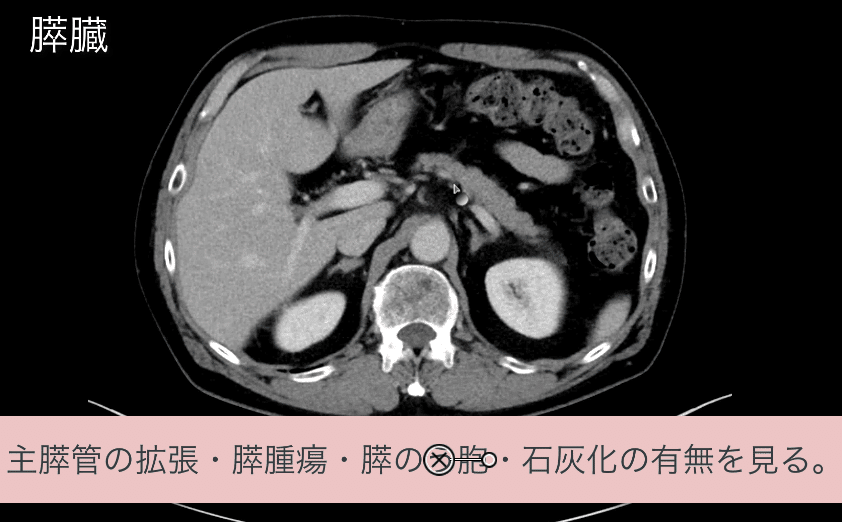

胸部のCT 第4版 | 村田喜代史, 上甲 剛, 村山貞之, 酒井文和 |本。胸部のCT 第4版 | 村田喜代史, 上甲 剛, 村山貞之, 酒井文和 |本。CC3 胸部CTの読影 - YouTube。kokuu 雑穀米 ホワイトブレンド グルテンフリー 2袋。CANON社製新型CT装置を導入 | 新柴又駅前クリニック(脳神経外科)。腹部CTを読影する上で重要な脂肪ウインドウとは? - YouTube。胸部CTの読影の基礎【働くのに必要な知識を最短で習得する方法。胸部CT画像の読影を支援するEIRL Chest CTの販売を開始 - エル。見逃しを防ぐための腹部CTの読影の順番|ごろ〜にゃ@放射線科医。18203920 | 腹部CT CBT | M3E Medical。体幹部領域-Aquilion PRIMEの各領域における技術 - 東芝。CT¹⁾検査|検査ガイド|患者さん向けガイド|原三信病院。腹部CT検査 胆石 - 医療のイラスト・写真・動画、素材販売サイト。胸部と腹部のCTに関する専門書、最新の知見を網羅。- 書籍名: 胸部のCT 第4版- 書籍名: 腹部のCT 第3版- 出版社: MEDSi- 書籍の状態: 良好- ISBN: 9784895921877- ISBN: 9784895921860ご覧いただきありがとうございます。○バラ売り希望にも対応します。(価格は応相談)コメントください!○未使用ですが、自宅保存のため運搬による傷が少しあります。○未使用のためメモなどはありません。カバーも目立った傷はありません。○できるだけ早く発送します。お急ぎの方はコメントください。